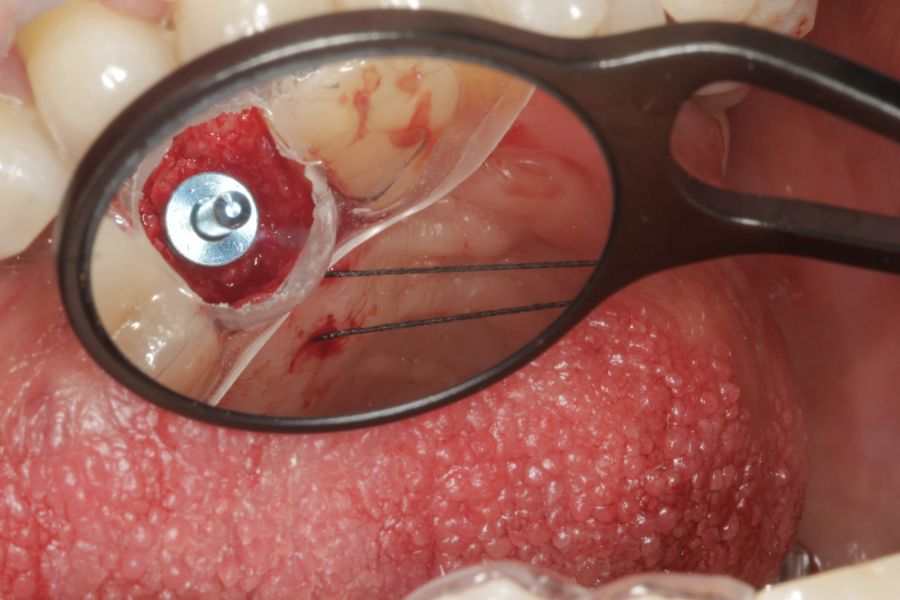

En cuanto a la rehabilitación protésica, en todos los casos se utilizó una prótesis atornillada con transepitelial para prótesis unitaria. La supervivencia de las prótesis fue del 100%, sin encontrarse fracaso en ninguna de ellas al igual que los implantes, con un tiempo de seguimiento de tres años. Durante el primer año, en las visitas de control, ninguno de los implantes mostró sangrado al sondaje ni inflamación de los tejidos periimplantarios. La media de la pérdida ósea en este punto fue de 0,32 mm (+/- 0,60) y la media de la pérdida ósea distal de 0,31 (+/- 0,48). A los dos años, no se registraron tampoco signos inflamatorios en ninguno de los implantes y la pérdida ósea mesial del conjunto fue de media de 0,38 mm (+- 0,54) y la distal de 0,64 mm (+/- 0,70). En la última visita a los 3 años, los tejidos periimplantarios siguieron estables, sin signos de inflamación y la media de la pérdida ósea mesial fue de 0,40 mm (+/- 0,53) y la distal de 0,69 (+/- 0,55) (Figura 5). En las Figuras 6-12 se muestra uno de los casos incluidos en el estudio.